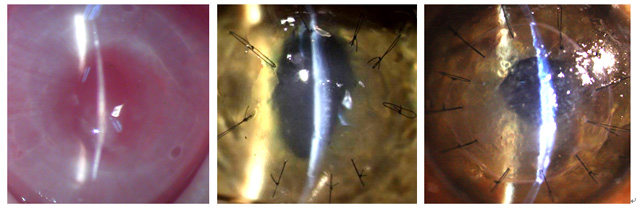

海大角膜组织工程实验室研制的组织工程角膜内皮在新西兰兔、家猫和猕猴移植中均获得成功

本站讯 由中国海洋大学角膜组织工程实验室研制的组织工程人角膜内皮,在新西兰兔角膜内皮移植成功